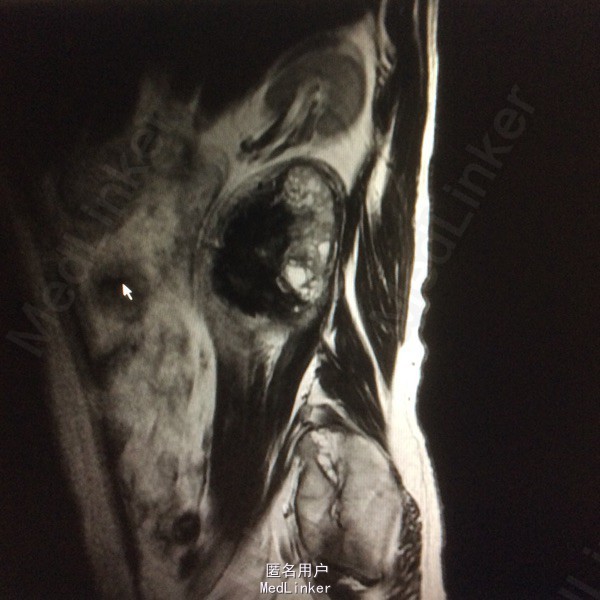

患者双下肢无明显浅感觉减退,肌力V级,肌张力不高,二便控制满意,病理征阴性。 腰椎核磁:腰1-4椎体右侧右肾下方团块状占位,大小约8#⃣6.8Cm,等T1长T2信号 腰椎Ct:占位周围见弧形钙化灶

腰椎神经鞘瘤 切除右侧横突,见腰2神经根延伸呈膜状,沿腰2神经跟出口将神经切断,完整取出肿物。